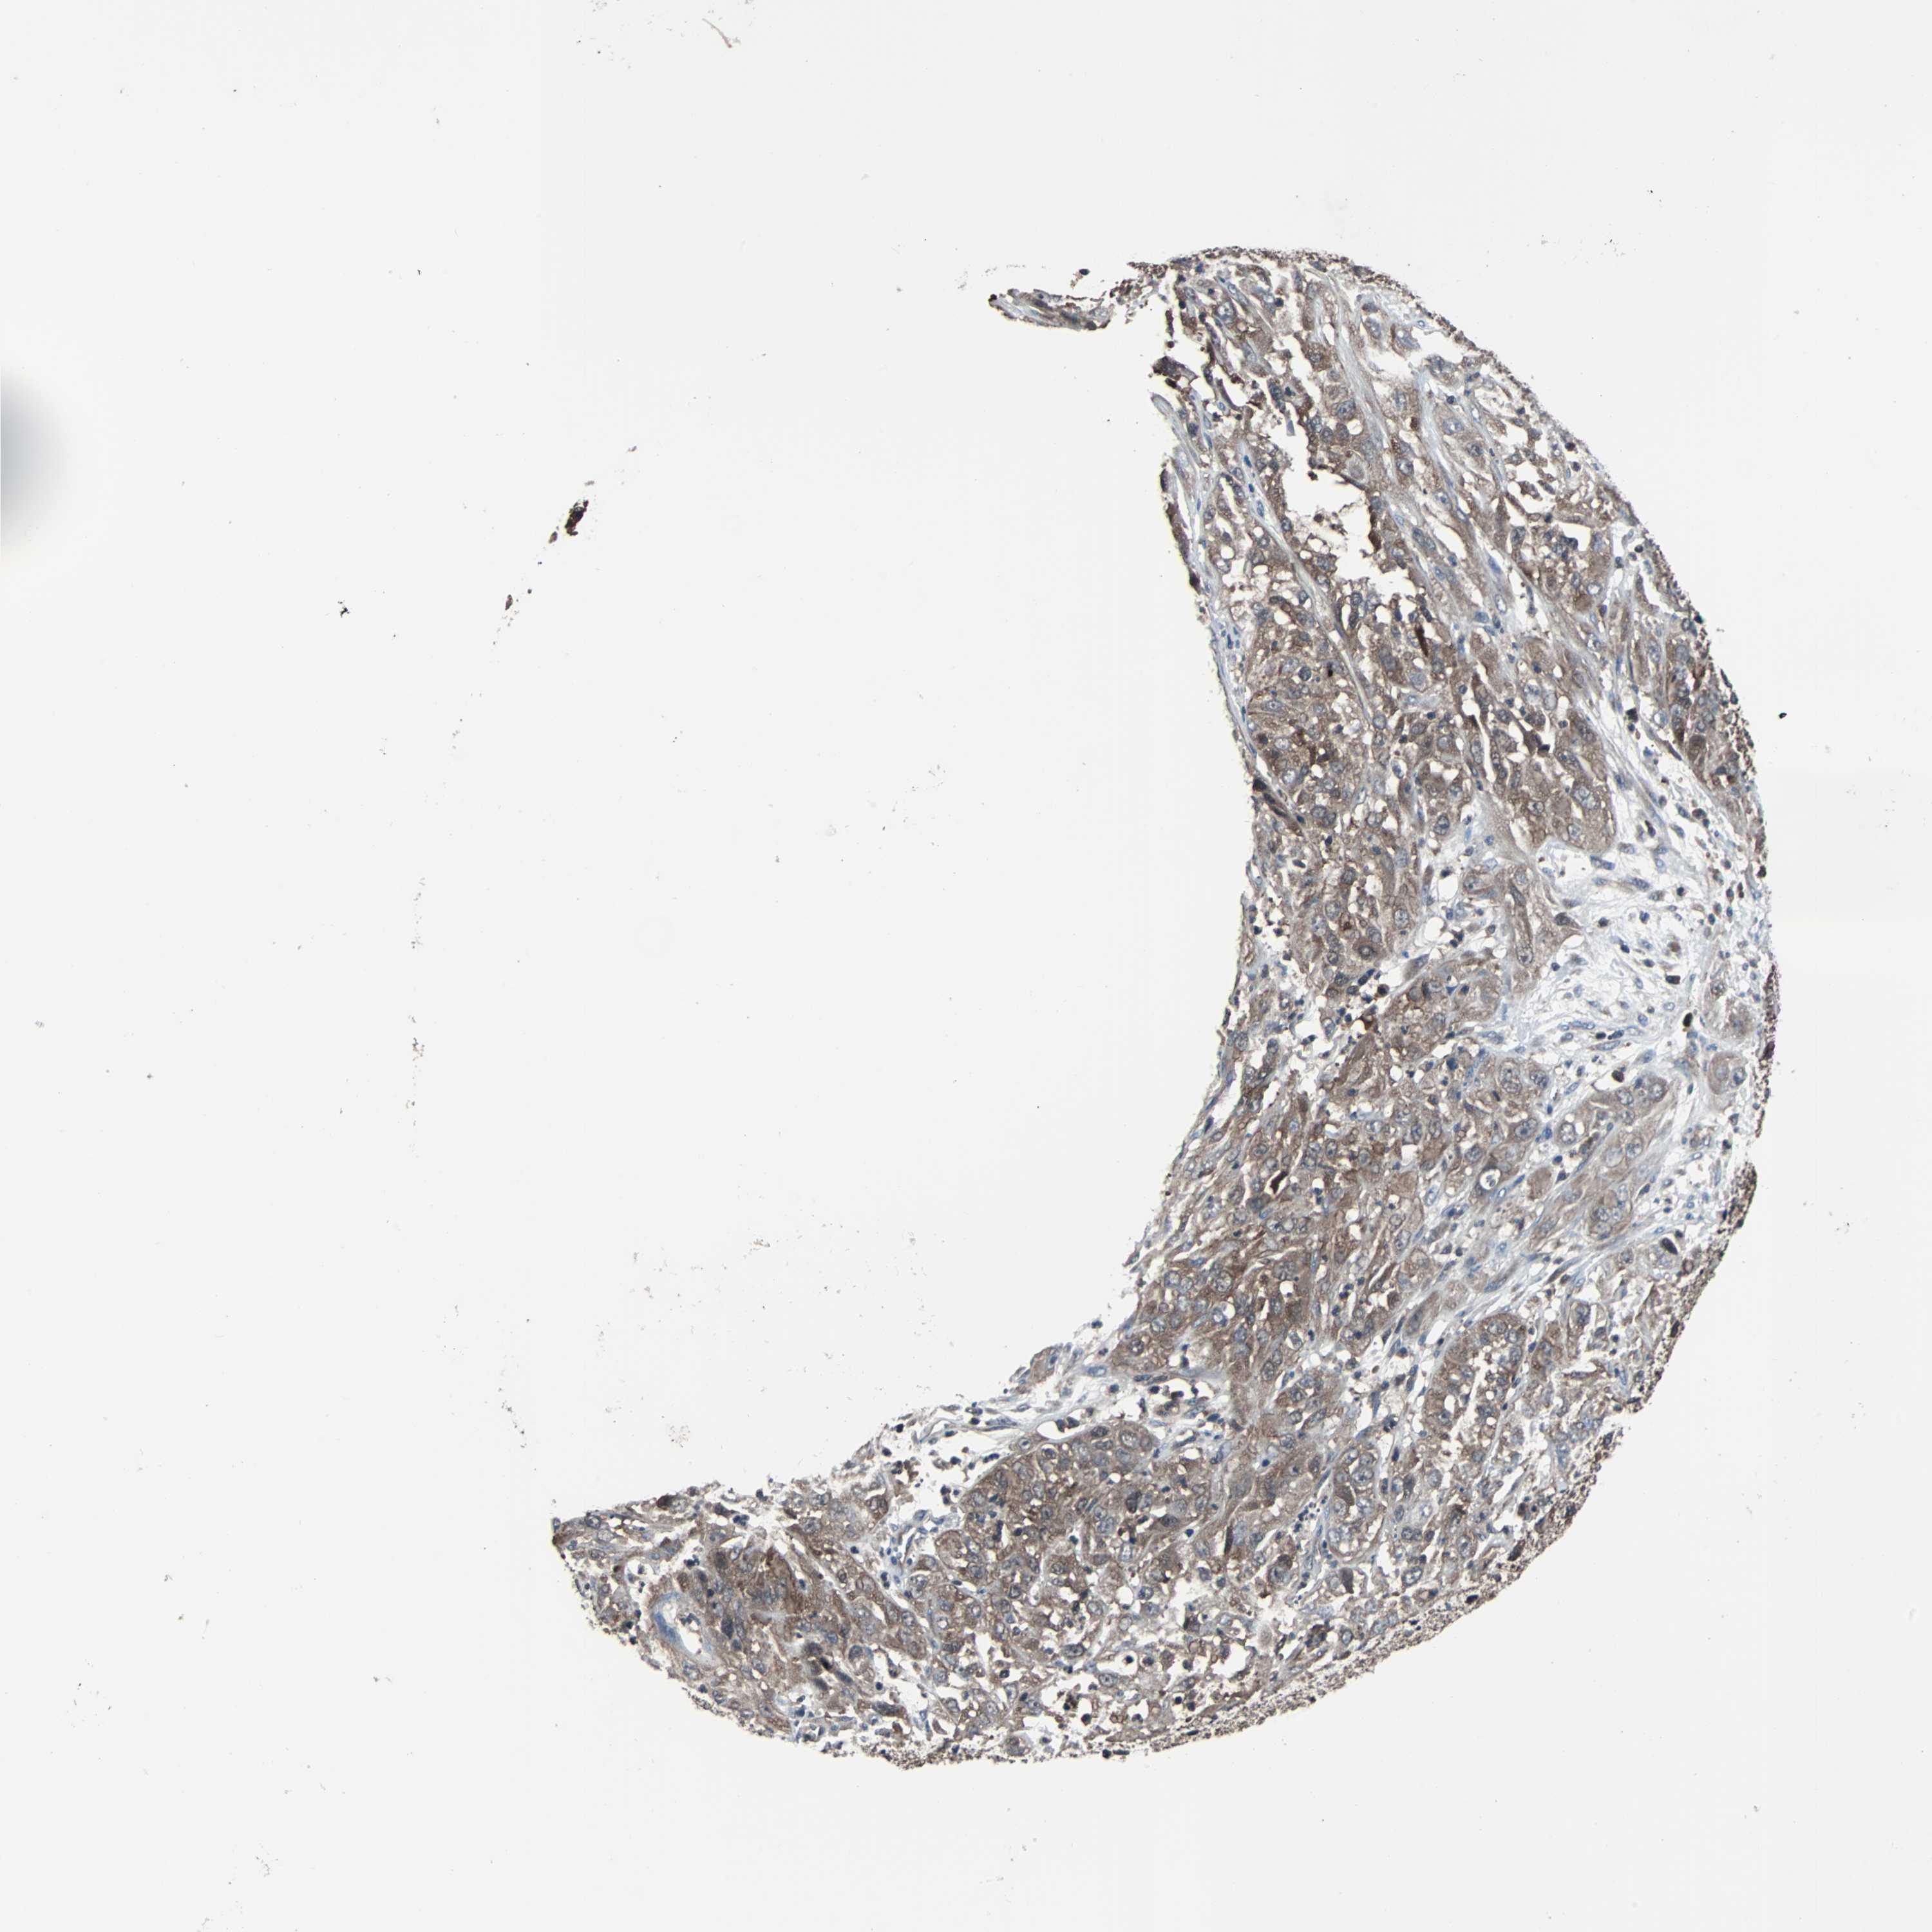

CERVICAL CANCER - Protein expressioni

A mouse-over function shows sample information and annotation data. Click on an image to view it in a full screen mode. Samples can be filtered based on level of antibody staining by selecting one or several of the following categories: high, medium, low and not detected. The assay and annotation is described here.

Note that samples used for immunohistochemistry by the Human Protein Atlas do not correspond to samples in the TCGA dataset.

Antibody stainingi

Antibody staining in the annotated cell types in the current human tissue is reported as not detected, low, medium, or high, based on conventional immunohistochemistry profiling in selected tissues. This score is based on the combination of the staining intensity and fraction of stained cells.

Each image is clickable and will lead to virtual microscopy that enables deeper exploration of all samples and also displays staining intensity scores, fraction scores and subcellular localization as well as patient and tissue information for each sample.

Antibody HPA003565

Antibody CAB005312

Staining

High

Medium

Low

Not detected

Intensity

Strong

Moderate

Weak

Negative

Quantity

>75%

75%-25%

<25%

None

Location

Nuclear

Cytoplasmic/membranous

Cytoplasmic/membranous,nuclear

Squamous cell carcinoma, NOS

Adenocarcinoma, NOS